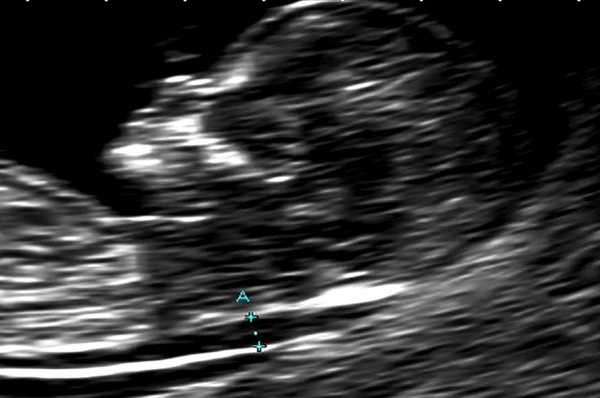

В основной группе численные значения расширенного воротникового пространства плода варьировали от 2,5 до 11,0 мм и превышали соответствующие показатели (5-й, 50-й, 95-й центиль) в группе сравнения в 11-12, 12-13 и 13-14 недель беременности (рис. 1).

Рис. 1. Увеличение толщины воротникового пространства

Из 175 плодов, у которых в сроке 11-14 недель беременности было выявлено расширение воротникового пространства, пренатальное или постнатальное кариотипирование для исключения хромосомных аномалий было осуществлено в 160 случаях. Из них хромосомные дефекты были обнаружены в 46/160 (28,8%) наблюдениях. У 114/160 женщин (71,2%) кариотип был нормальным. В 15 случаях хромосомный набор плода/новорожденного остался за пределами наших знаний из-за отказа пациентки от инвазивной диагностической процедуры или из-за отсутствия достаточного количества метафаз в биоптате хориона.